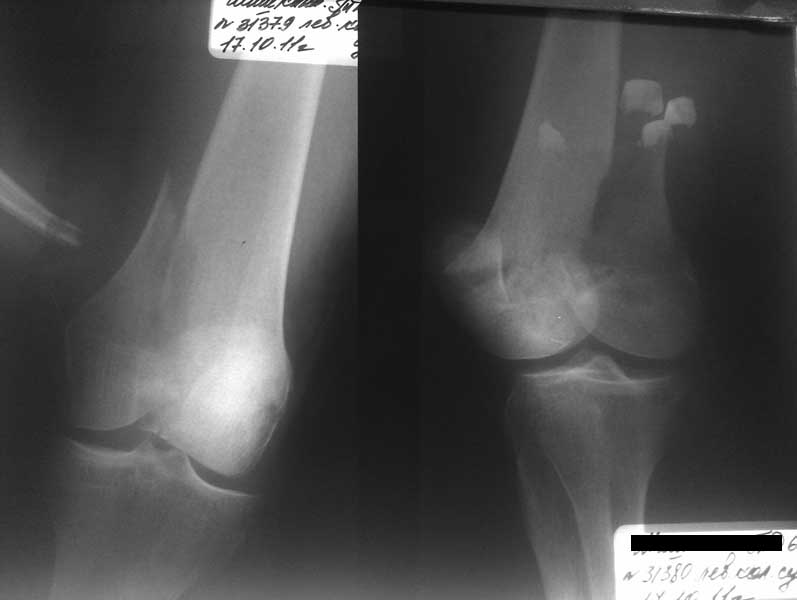

Представленный снимок не дает полную информацию. Там вроде простой перелом, но на самом деле, кроме смещенного (латерального, возможно медиального?) мыщелка на второй проекции имеется медиальный короткий дистальный фрагмент в флексии. Надо было сделать прямой снимок с захватом малоберцовой, который ориентировал бы стороны. Без КТ обычный снимок в дистракции поможет разобраться в топографии фрагментов.

Во время фиксации надо соблюдать осторожность, особенно с коротким фрагментом на другой стороне. Обычно на прямой проекции трудно заметить флексионную деформацию мыщелка и упускается адекватная фиксация. Без пластины винты не смогут удержать, и мыщелок на второй стороне может сместиться. Для фиксации надо развернуть мыщелок и удержать винтами. Качество межмыщелковой репозиции надо проконтролировать артротомией. Из всех доступов только передне-латеральный доступ (Swashbuckler) даст обзор для ревизии качества фиксации, который в будущем может быть использован для артропластики.

Кстати, из вашего снимка, если отмечены вашим рентгенологом правильно, тогда получается снимок левого колена, и, соответственно, длинный переходящий в диафиз мыщелковый фрагмент находится медиально. Если так, тогда меняется сценарий фиксации!!!

И не обратите, коллега, пока не сделаете четкие анфасные снимки (лучше с дистракцией) где будет четко визуализироваться малоберцовая кость. Думается, что и КТ здесь будет уместно, дабы не пропустить возможное флексионное повреждение (перелом Hoffa).